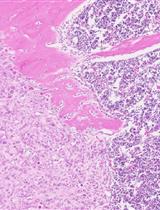

By day 4 of the experiment, in spheroids after the IL-6–induced dedifferentiation, stand-alone tumor cells with the RFP+CD44+CD24+ phenotype (progenitor cells) or RFP+CD44+CD24– phenotype (stem cells) were observed, as were foci consisting of several tumor cells having the RFP+CD44+CD24+ phenotype (Figure 12A). In the spheroids incubated with IL-6 and the mixture of miRNAs, only a few RFP+CD44+CD24+ cells and RFP+CD44–CD24+ (differentiated) cells were noted within the spheroid (Figure 12B).

Figure 12. Representative images of the spheroid on the fourth day of the experiment. (A) The control (induction by IL-6) and (B) experiment (induction by IL-6 and treatment with the mixture of miRNAs). Cancer T47D_Red cells are red, CD44+ cells are green, CD24+ cells are magenta, and nuclei are stained with DAPI (blue).